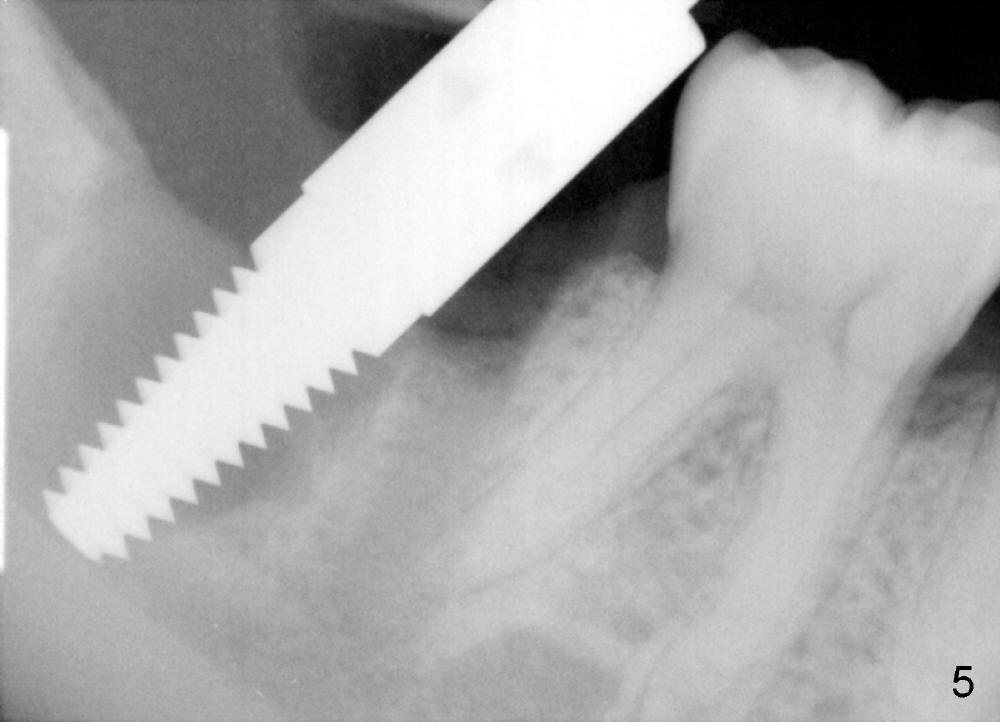

P: 31 Ext, immediate implant in the mesial socket (Fig.2), 14 redo bu, crown, treatment plan discussed

A: after obtaining verbal and written sx consent, Mepivacaine 54 mg, Xylo 34 mg, Septo 68, Epi 34 mcg infiltration, separated gingiva with periotome, pt had pain, Marcaine 9 mg, Xylo 34 mg, Epi 26 mcg infiltration and intraligamental injection, routine ext with forceps, curettage with serrated curette, lot of granulation tissue, until the bottom of the socket, close to presumptive inferior alveolar canal, tissue apparently running mesiodistally, easily removed without active hemorrhage, distal root has abundant calculus, distal socket apparently too large for implantation, copious irrigation, placed Clindamycin gauze x3, mesial socket flat (B-L width is much bigger than M-L one), inserted D1,2 spreader and D2 socket formers with difficulty, handles contact #30 distal crown, inserted RT 2,3,4 and tapered osteotomes 5x18 and 6x18 mm, trying to move the septum distally with much help, inserted 4.5x20 mm tap at 17 mm depth, stable, PA taken: tap close to #30 distal root, approaching IAN (Fig.3), changed to 5x17 tap at 14 mm without stability, when 6x17 tam is inserted at 14 mm, it is stable, PA taken: tap very close to #30 distal root (Fig.4), removed the tap (mesial wall of the mesial socket: no obvious perforation with distal root of #30) and droppd it  into in the distal socket, PA: tap tip overlaps IAN canal (Fig.5), discussed possible nerve injury and touching neighboring root, pt agreed to abort implant placement and place bone graft. placed collagen plug (CollaForm-Plug, Absorbable Collagen Wound DRef CFP1020_5, Lot CFP1020_1301)) in the bottom of the socket (to make room for nerve regeneration), inserted ~.6 cc CANCELL Oss (Mineralized Cancellous Human Allograft, distributed by Implandent LTD, .850-1 mm, 03-0494763/03-0494749, Product Code 06412201, mixed with .3 mg Osteogen (300-400 micron, Osteoconductive Synthetic Bioactive Resorbable Graft, Impladent LTD) into sockets, placed another collagen plug on the top of bone graft, 4-0 chromic gut suture (figure 8 and 1 interrupted), perio dressing, hemostatic. Pt was doing well. POI (oral) and extra gauze given. Continue Amoxicillin, Chlorhexidine, Medrol and Norco, Vitamin B complex recommended